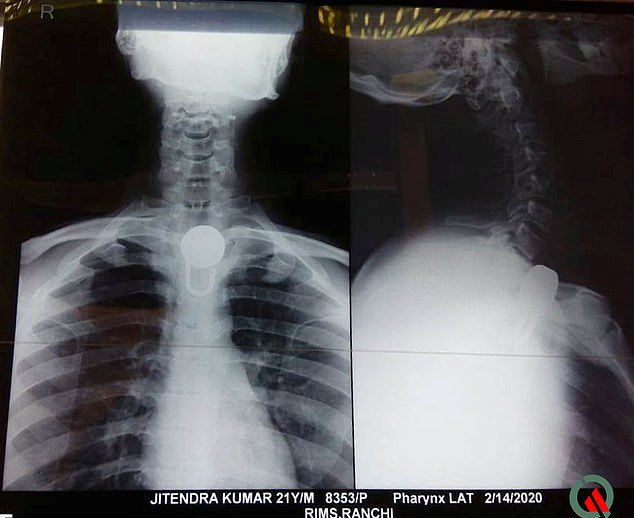

Εκεί οι γιατροί του έκαναν ακτινογραφία, εντόπισαν την ακριβή θέση του λουκέτου στο λαιμό του και κατάφεραν να το αφαιρέσουν.

Τώρα ο Jitendra συνεχίζει να νοσηλεύεται στο νοσοκομείο ενώ για κάποιο χρονικό διάστημα οι γιατροί λένε ότι θα τρέφεται μόνο μέσω ρινικού σωλήνα.